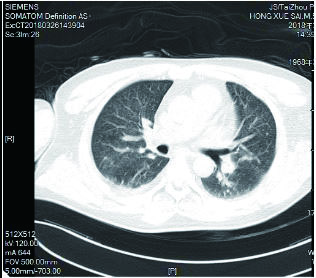

1.2 临床表现和检查患者初期有咳嗽症状,但未在意,患者回家24 h后咳嗽症状加重,伴胸闷气喘,全身大汗淋漓,家属立即将其送至本院急诊,为进一步诊治拟“有机氟中毒”收住入院。入院时体检:神志清楚,T:36.5℃,R: 57次/min,BP: 146/71 mmHg,胸廓对称无畸形,呼吸急促,听诊双肺呼吸音清晰,可闻及大量湿性啰音,心率112次/min,心律齐,心音正常,各瓣膜听诊区未闻及病理性杂音及心包摩擦音,四肢关节正常,双下肢无水肿,深浅生理反射正常,病理反射阴性,脑膜刺激征阴性。辅助检查:白细胞计数10.45×109/L,中性粒细胞91.9%;C-反应蛋白14.81 mg/L, 无创机械通气支持下血气分析pH7.28,PCO2 50 mmHg, PO2 57 mmHg, Lac 3.0 mmol/L(FiO2 50%),为Ⅱ型呼吸衰竭,给予无创呼吸机辅助呼吸、激素冲击、解痉平喘等抢救治疗。急诊胸部CT检查提示:两肺散在斑片状模糊影,密度不均,边界不清(图 1),进ICU床边胸片提示:两肺散在斑片状模糊影(图 2)。根据GBZ5—2016《职业性氟及其无机化合物中毒的诊断》的诊断标准,该患者诊断为职业性急性重度有机氟中毒。

| 图 1 3月10日胸部CT |